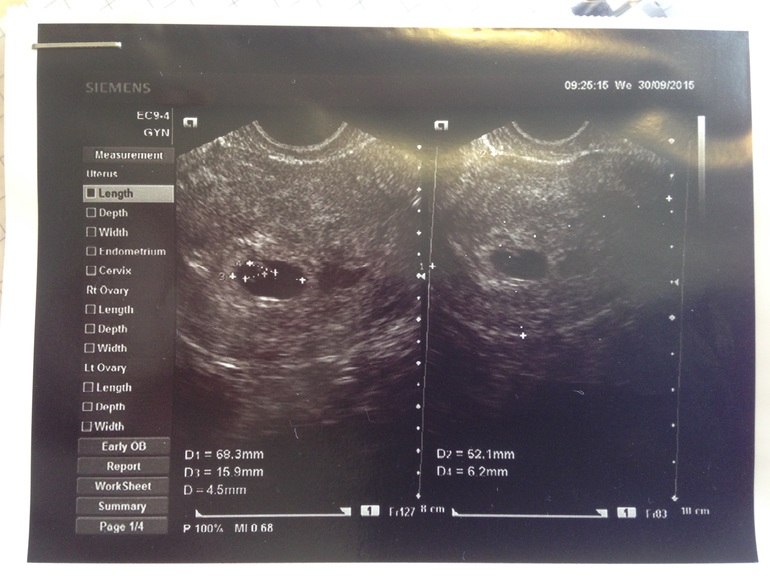

Вчера такой пост создавала, но видимо я его случайно удалила. Так вот мое первое узи: мешочек и эмбриончик я вижу отчетливо..... А вот смущает , рядом тоже мешочек или что это? Я в интернете нашла похожее , типа двойня на 5 неделе. Узистка вообще ничего не сказала, кроме как все хорошо , только матка чуть в тонусе. Девочки, ваши предположения? Фото под кат